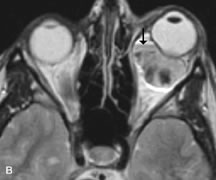

Application of a 90° RF pulse brings the excited nuclei into phase so that the net vector of their magnetic moments is directed perpendicular to the static magnetic field. Shortly thereafter, the magnetic moments of the nuclei spread out and point in different directions, leading to a loss of phase coherence and a resultant decay in signal intensity amplitude. The T2, or spin-spin relaxation time, is the rate of decrease in the signal of these excited nuclei as a result of the interaction and transfer of energy to unexcited adjacent nuclei. T2 ranges from a few milliseconds to a few hundred milliseconds and, for a given tissue, is always less than the Tl relaxation time. T2-weighted orbital images are easily recognized by a high-intensity signal from the vitreous (Fig. 9).5,8,16